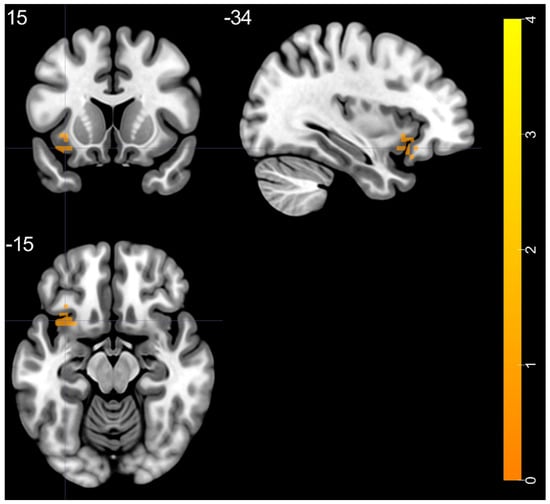

| Brain Regions | Peak T-Scores | MNI Coordinates | Cluster Size (Voxels) | ||

|---|---|---|---|---|---|

| x | y | z | |||

| BD > HC | |||||

| left insula—BA 47 | 4.228 | −36 | 15 | −15 | 37 |